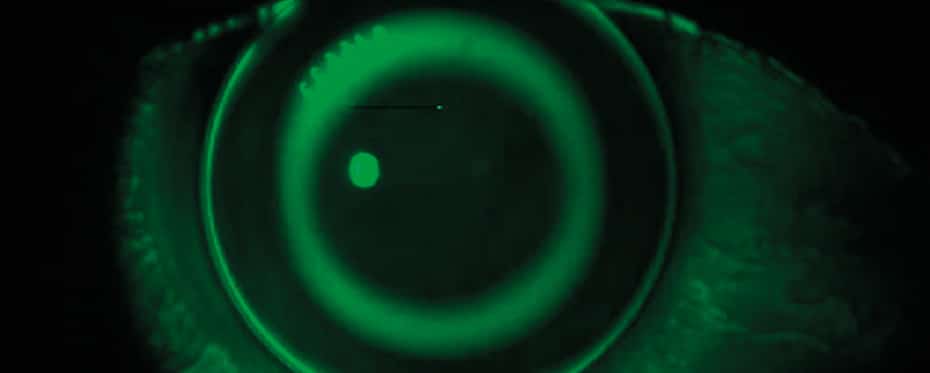

过夜的矫正器是一种改进或进步隐形眼镜的矫形器学(OK)的临床技术(OK),自20世纪60年代以来一直在全球范围内使用。它是一种用于治疗眼睛条件的角膜屈光治疗,主要是近视(短视),但也是老花眼(长视线),远视(与近物体附近的年龄相关的能力)和散光(一个 […]